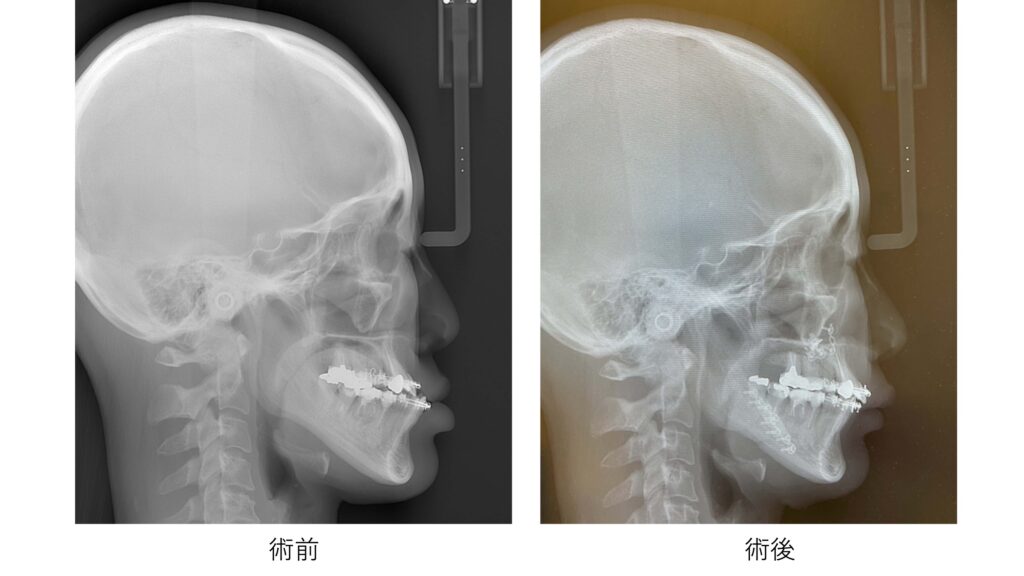

下に示したのが、手術前と手術後の側面セファログラム(横顔のレントゲン写真)です。骨の位置関係を比較することで、あごがどのように移動し、顔全体のバランスがどのように変化したかを客観的に確認することができます。

上あごを前方に移動させたことで、鼻の付け根から口元にかけての立体感が改善し、一方で下あごやあご先は出過ぎない位置に収まっています。その結果、横顔全体のバランスがより自然な印象になっていることがわかります。